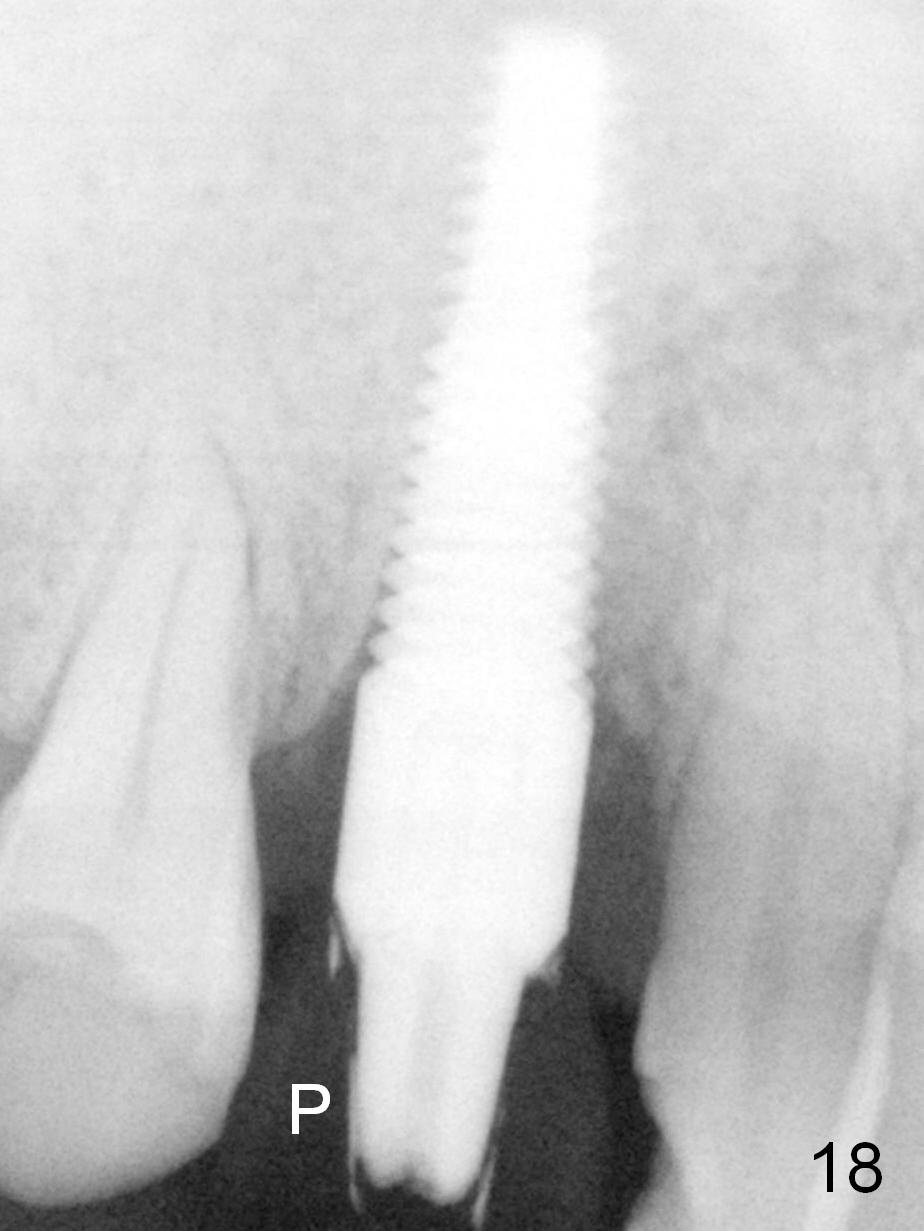

Three months postop, the implant appears to have osteointegrated with disappearance of the distal gap (Fig.18).  P: provisional.  The crestal bone is stable 3 Years 7 Months Post Cementation (Fig.21).